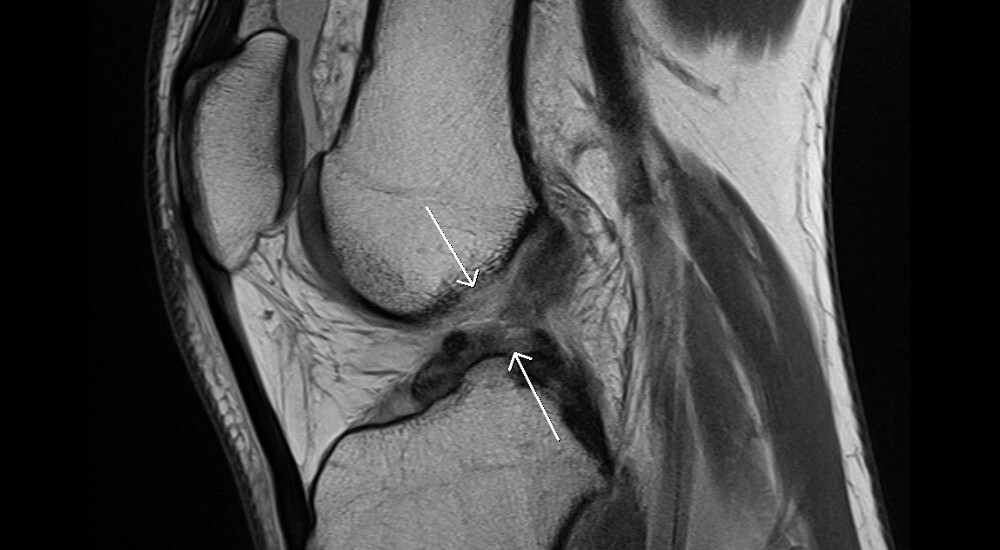

Las lesiones del ligamento cruzado anterior son de las mas comunes para los deportistas, y también de las mas dolorosas. Ahora un desarrollo de nanotecnología promete la deseada solución de reemplazar ligamentos.

El ligamento cruzado anterior es especialmente sensible para un deportista, ya que no puede curarse y las operaciones para recuperar el movimiento dejarán dolor en el paciente hasta el resto de su vida. La Universidad Northwestern cree poder reemplazar ligamento cruzado anterior dañado, por otro con nanotecnología, creados a base de fibras de poliéster entrelazadas.

La fuerza tensil de este tipo de tejido es similar a la del ligamento natural, pero en sus extremos se fusionan en un material antioxidante poroso y con nanocristales de calcio. En pruebas con conejos se hicieron agujeros en los huesos para pasar los ligamentos; en el periodo de recuperación se comprobó que el hueso se fusionaba con los ligamentos en sus extremos porosos. Con el tiempo suficiente, el ligamento artificial debería formar parte de la estructura de la rodilla como si fuera el original. Pero antes aún faltan mas estudios para su implementación en seres humanos.